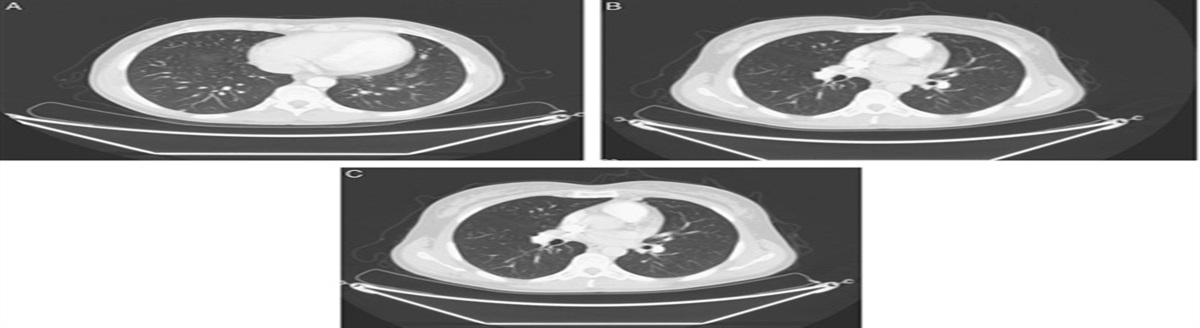

Figure 1Figure 1:

Comparison of pulmonary lesions. A, Lung computed tomography before chemotherapy. B, Lung computed tomography 3 months after chemotherapy. C, Lung computed tomography 5 months after chemotherapy.

In March 2019, the CT scan showed a partial response (PR) to treatment (reduction of lung lesions); normal hCG levels (3 mIU/mL) were observed. After discussing with the patient, 4 more cycles were administered. In May 2019, the CT scan revealed a further lung response, with lower blood hCG levels (<0.05 mIU/mL). Chemotherapy was stopped and a short-term follow-up was begun, with the patient undergoing a CT scan and assessment of hCG blood levels every 3 months. At the latest follow-up, in February 2020, the CT scan detected a further size reduction of pulmonary lesions (Figs. 1B, C) (maximum diameter 2 mm), while blood hCG value was 1 mIU/mL.